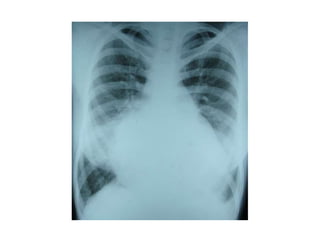

Foto Rontgen Dada

• Pada foto lateral terlihat daerah retrosternal

terisi, akibat pembesaran ventrikel kanan.

• Dilatasi atrium kanan.

• Segmen pulmonal menonjol, corakan vaskular

paru prominen.